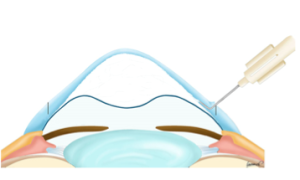

- A) Cross-link (Crosslinking – CXL) de córnea no Tratamento do Ceratocone

O procedimento “Cross-link ou Corneal Cross-Linking” consiste no uso de radiação ultravioleta, associada a uma substância chamada riboflavina, aumentando a rigidez biomecânica da Córnea. No Crosslinking ocorre o fortalecimento das fibras de colágeno, que representam as pontes de sustentação da Córnea. Com o aumento da resistência, diminui-se a elasticidade da córnea, reduzindo a chance de a progressão do Ceratocone.

2) Como é feito o Crosslink (Crosslinking)?

Modelo esquemático das 6 camadas da Córnea:

No protocolo tradicional de Crosslinking, o procedimento é realizado em um centro cirúrgico, e após anestesia tópica (com colírio), o Epitélio, camada mais externa da Córnea, é removido. Na sequência gotas de Riboflafina (Vitamina B2 – que funciona como substância foto-sensibilizadora) são aplicadas na córnea por 30 minutos para que penetre no estroma, camada de sustentação da córnea. Após a verificação da saturação da camada do Estroma da Córnea, procede-se com a aplicação de radiação ultravioleta A (UVA) por 30 minutos, com comprimento de onda de 370 nm e 3mW/cm2. Durante esta etapa mais gotas de vitamina B2 são utilizadas.

O procedimento é concluído com aplicação de uma lente de contato protetora, que vai proteger a Córnea e permitir alívio de possível desconforto local, funcionando como um curativo na Córnea.